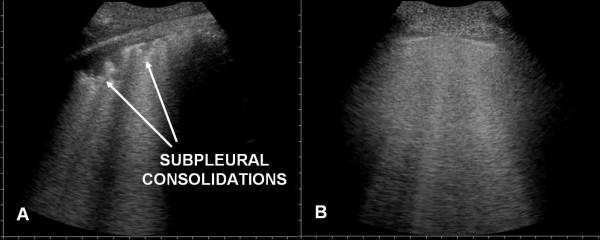

Ultrasound examination was focalised on finding in the two groups the presence of: 1) alveolar-interstitial syndrome (AIS) 2) pleural lines abnormalities 3) absence or reduction of "gliding" sign 4) "spared areas" 5) consolidations 6) pleural effusion 7) "lung pulse".AIS was found in 100% of patients with ALI/ARDS and in 100% of patients with APE (p = ns). Pleural line abnormalities were observed in 100% of patients with ALI/ARDS and in 25% of patients with APE (p < 0.0001). Absence or reduction of the 'gliding sign' was observed in 100% of patients with ALI/ARDS and in 0% of patients with APE. 'Spared areas' were observed in 100% of patients with ALI/ARDS and in 0% of patients with APE (p < 0.0001). Consolidations were present in 83.3% of patients with ALI/ARDS in 0% of patients with APE (p < 0.0001). A pleural effusion was present in 66.6% of patients with ALI/ARDS and in 95% of patients with APE (p < 0.004). 'Lung pulse' was observed in 50% of patients with ALI/ARDS and in 0% of patients with APE (p < 0.0001). All signs, except the presence of AIS, presented a statistically significant difference in presentation between the two syndromes resulting specific for the ultrasonographic characterization of ALI/ARDS.

超声检查重点在于在两组中发现以下情况:1)肺泡-间质综合征(AIS);2)胸膜线异常;3)“滑动”征缺失或减弱;4)“ spared区域”;5)实变;6)胸腔积液;7)“肺搏动”。AIS在100%的ALI/ARDS患者和100%的APE患者中均有发现(p=无显著性差异)。胸膜线异常在100%的ALI/ARDS患者和25%的APE患者中观察到(p<0.0001)。“滑动”征缺失或减弱在100%的ALI/ARDS患者和0%的APE患者中观察到。“ spared区域”在100%的ALI/ARDS患者和0%的APE患者中观察到(p<0.0001)。实变在83.3%的ALI/ARDS患者中存在,在0%的APE患者中存在(p<0.0001)。胸腔积液在66.6%的ALI/ARDS患者和95%的APE患者中存在(p<0.004)。“肺搏动”在50%的ALI/ARDS患者和0%的APE患者中观察到(p<0.0001)。除AIS的存在外,所有体征在两种综合征之间的表现上均存在统计学显著差异,从而对ALI/ARDS的超声特征具有特异性。

Pleuroparenchimal patterns in ALI/ARDS do find a characterization through ultrasonographic lung scan. In the critically ill the ultrasound demonstration of a dyshomogeneous AIS with spared areas, pleural line modifications and lung consolidations is strongly predictive, in an early phase, of non-cardiogenic pulmonary edema.

ALI/ARDS中的胸膜实质模式可通过超声肺部扫描进行特征描述。在危重症患者中,超声显示不均匀的AIS伴 spared区域、胸膜线改变和肺实变在早期强烈提示非心源性肺水肿。